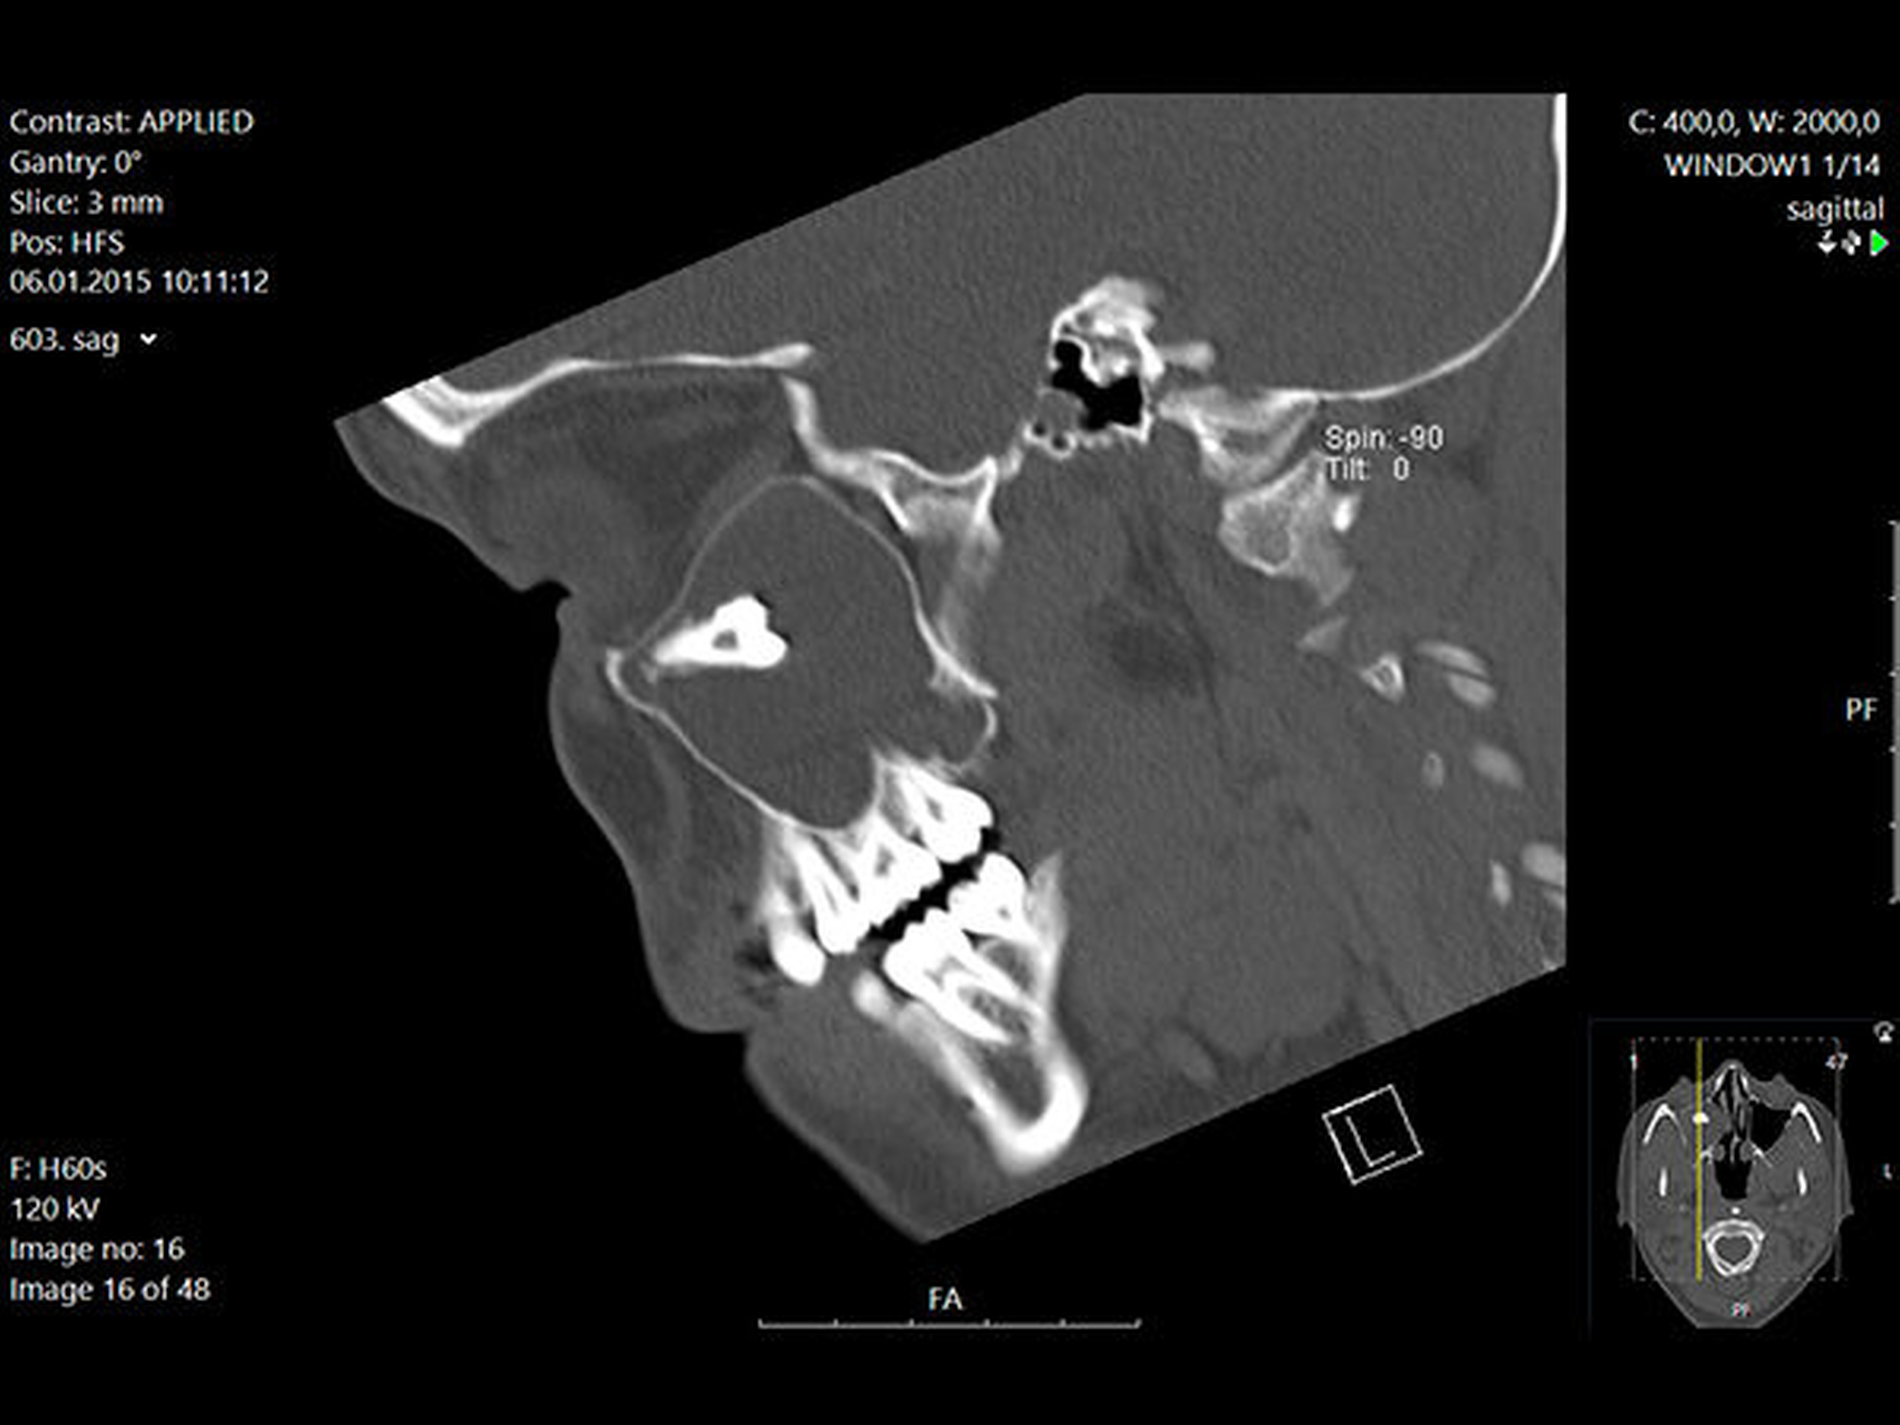

In der regionalen Klinik (Winterberg-Krankenhaus Saarbrücken) wurde zusätzlich eine kontrastmittelunterstützte Computertomografie der Nasennebenhöhlen durchgeführt (Abbildungen 2 und 3), die den Befund bestätigte und präzisierte.

Intraoperativ entleerte sich reichlich eingedicktes Sekret. Die dort ebenfalls veranlasste postoperative Histologie ergab die Kombination einer Kieferhöhlenzyste (respiratorisches Epithel) mit einer odontogenen Zyste (mehrschichtiges nicht keratinisiertes Plattenepithel). Der weitere Verlauf war erfreulicherweise unkompliziert.